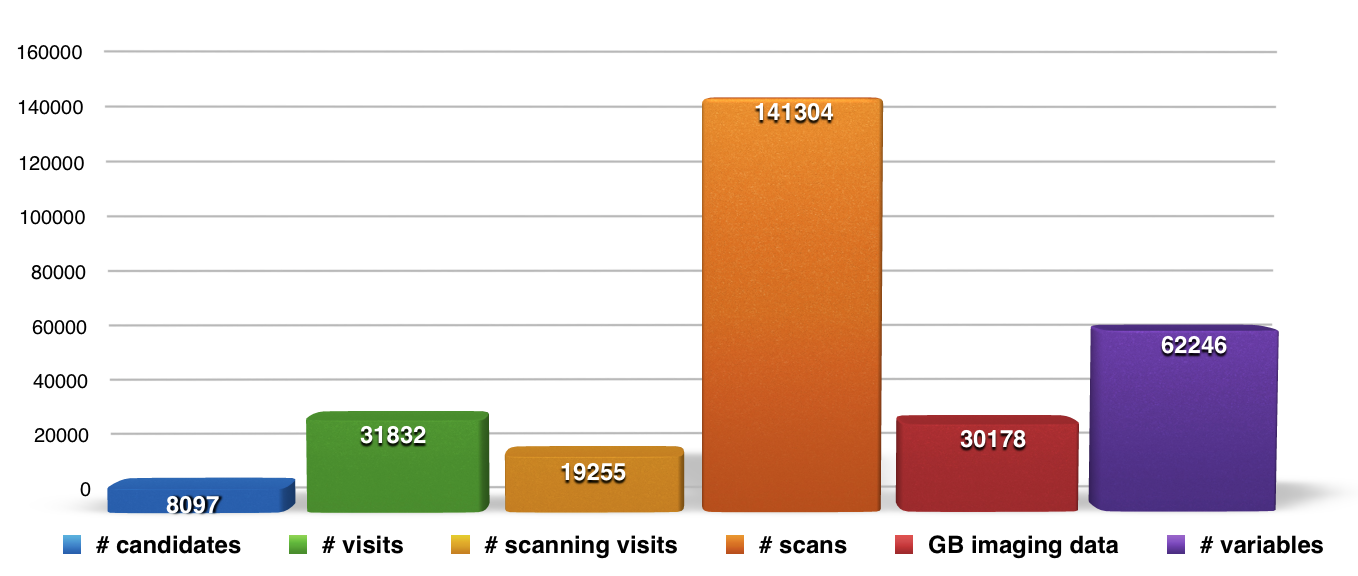

Summary Statistics

LORIS summary statistics